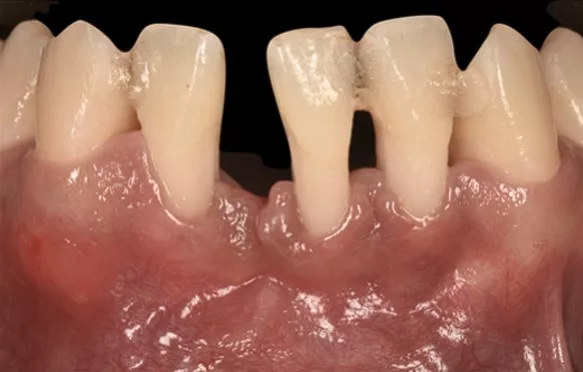

Préalable à tout traitement parodontal, la thérapeutique initiale, non chirurgicale, cherche à décontaminer les surfaces des racines dentaires, et notamment les zones situées sous la gencive. En effet les bactéries adhèrent très fortement à ces régions. Leur persistance, si elles ne sont pas rapidement éliminées, produit un effet pathogène (inflammation, abcès) pour les tissus de support des dents (gencive et tissu osseux).

Des bains de bouche (antiseptiques) ou des antibiotiques ne suffisent pas à les éliminer. Aussi des techniques manuelles ou ultrasoniques, indolores, sont indispensables décontaminer les surfaces colonisées par la plaque et le tartre.